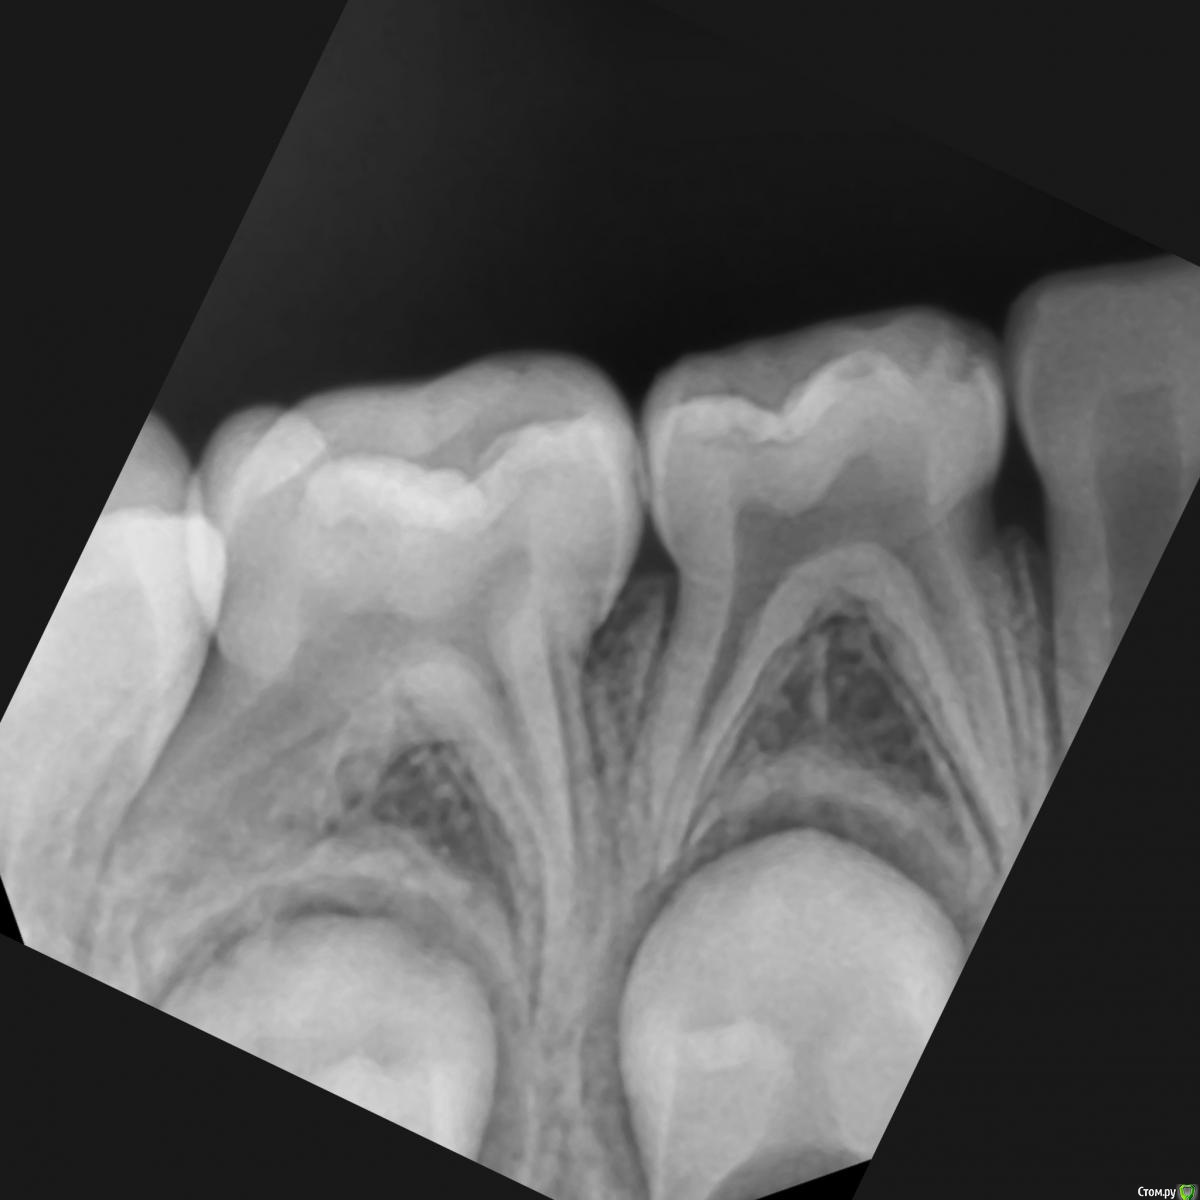

CRAZYDUCK Опубликовано 22 мая, 2018 Автор Поделиться Опубликовано 22 мая, 2018 (изменено) И про короночки ловите. 8.4 и 8.5 ранее ( около двух лет назад ) лечены методом витальной ампутации . Реставрации обширные плюс начался кариес контактных поверхностей . Два года назад я не применяла так широко в практике своей Коронки ( сейчас бы покрыла сразу после ампутации). Изменено 22 мая, 2018 пользователем CRAZYDUCK 1 Ссылка на комментарий

crown Опубликовано 22 мая, 2018 Поделиться Опубликовано 22 мая, 2018 8.4 похоже что есть изменения в бифуркации? Да надо возвращаться к коронкам. Вы где учились их ставить? Ссылка на комментарий

CRAZYDUCK Опубликовано 23 мая, 2018 Автор Поделиться Опубликовано 23 мая, 2018 В нижних 4 часто такая зона, даже в интактных. Я тоже на эту зону всегда недоверчиво смотрю. Я напишу Вам в личку позже где училась . 8.4 похоже что есть изменения в бифуркации? Да надо возвращаться к коронкам. Вы где учились их ставить? Ссылка на комментарий

CRAZYDUCK Опубликовано 24 мая, 2018 Автор Поделиться Опубликовано 24 мая, 2018 В этом клиническом случае хочу обратить внимание коллег на покрытие 8.5 зуба коронкой ( что необычного видите ?). И на использование флосса, чтобы заправить платок дистально за 4.6 . 4.6 начальный кариес , но зуб дистально ещё был прикрыт десной ( фото до лечения не делала без коффердама). Раньше во время работы в эту дистальную зону «трамбовала» Фумку . Следила , чтобы не подтекало . Но !!!!Очень удобно эту десну заправлять флоссом - ничего не течёт 1 Ссылка на комментарий

CRAZYDUCK Опубликовано 24 мая, 2018 Автор Поделиться Опубликовано 24 мая, 2018 8.5 ранее лечен методом витальной ампутации( 1,5 года назад ), но реставрация обширная . Не выдерживает жевательную нагрузку . 2 Ссылка на комментарий